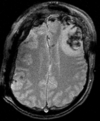

Within Exam:

Exam 1 PD aligned to T1

Exam 1 GRE aligned to T1

Exam 1 DWI aligned to T1